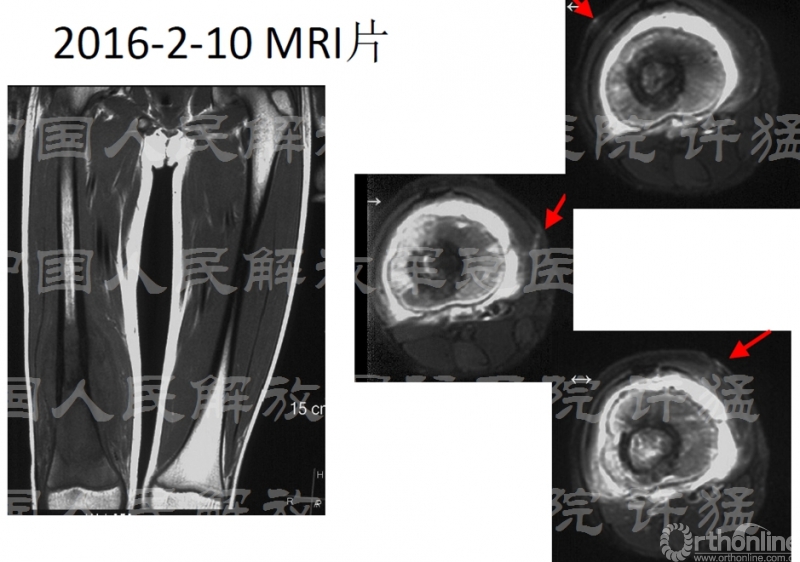

治疗前相关检查:

核磁显示穿刺通道有污染伸膝装置的可能